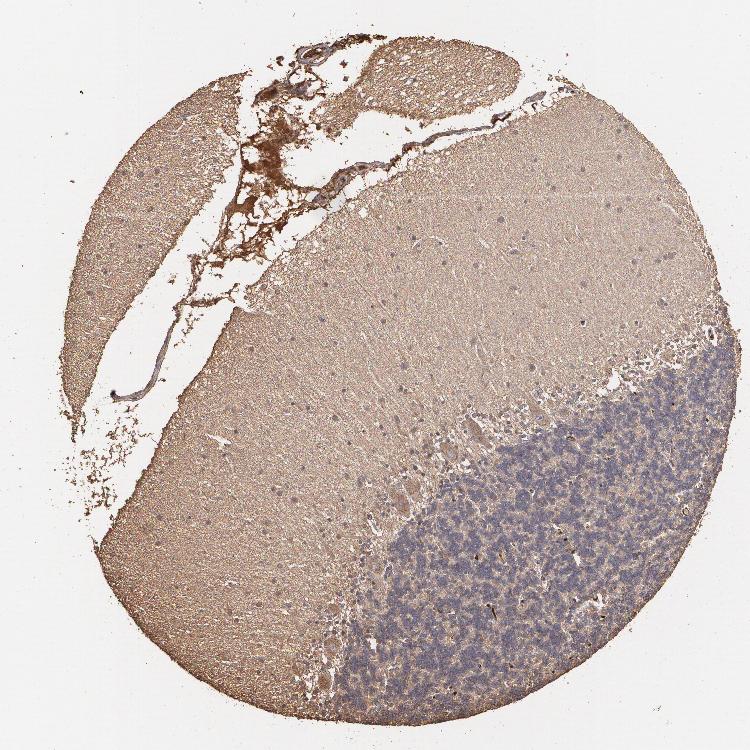

CEREBELLUM - Antibody stainingi

Antibody staining in the annotated cell types in the current human tissue is reported as not detected, low, medium, or high, based on conventional immunohistochemistry profiling in selected tissues. This score is based on the combination of the staining intensity and fraction of stained cells.

Each image is clickable and will lead to virtual microscopy that enables deeper exploration of all samples and also displays staining intensity scores, fraction scores and subcellular localization as well as patient and tissue information for each sample.

Antibody HPA001610

Purkinje cells Medium

Cells in granular layer Medium

Cells in molecular layer Medium